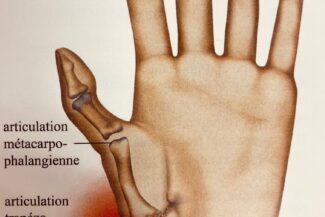

Prothèse trapézométacarpienne pour rhizarthrose du pouce

La prothèse trapézométacarpienne est une option chirurgicale utilisée pour traiter la rhizarthrose, une forme d’arthrose touchant la première articulation trapézométacarpienne du pouce. La rhizarthrose est caractérisée par la dégradation du cartilage articulaire et provoque des douleurs et une perte de mobilité dans le pouce. Lorsque les traitements conservateurs, tels que les médicaments et la thérapie physique, ne soulagent pas suffisamment les symptômes, la chirurgie peut être envisagée. La prothèse trapézométacarpienne est l’une des options chirurgicales disponibles.